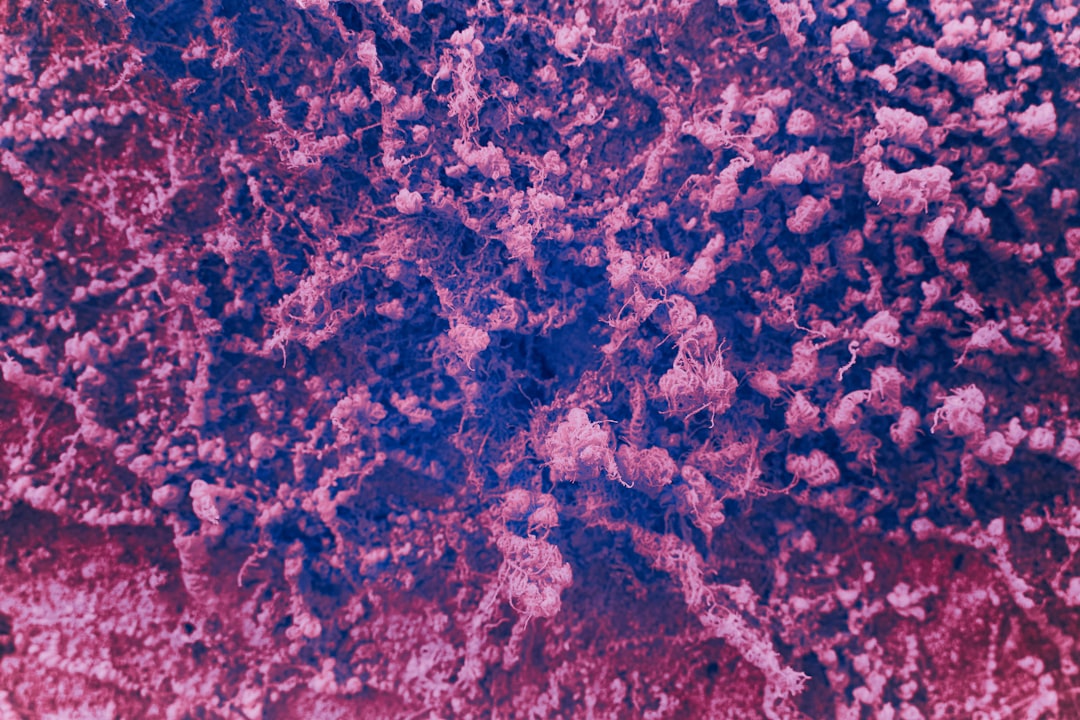

잠복결핵확인서란, 결핵균에 감염되었으나 현재 활성화된 결핵이 아닌 상태에서 발급되는 서류입니다. 이 서류는 주로 기관이나 학교, 직장에서 결핵 예방을 위한 검사의 일환으로 요청됩니다. 잠복결핵 확인서는 감염 여부에 대한 공식적인 증명서로 많은 곳에서 중요하게 다루어집니다. 특히 최근 들어 건강 관리의 중요성이 높아지는 가운데, 이 확인서는 매우 유용한 역할을 하고 있습니다.

잠복결핵확인서를 발급받기 위해서는 몇 가지 요건이 있습니다. 우선, 일반적으로 건강검진을 받아야 하며, 보통은 결핵 검사를 포함한 건강검진을 진행합니다. 이 검사에서 음성으로 확인되어야만 잠복결핵확인서를 발급받을 수 있습니다. 검사 종류로는 주로 튜베르쿨린 피부검사(TST)나 IGRA 혈액검사 등이 사용됩니다.